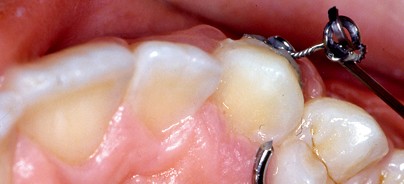

Bishara7 berichtete über ähnliche Rezidive der Eckzahnstellung, die durch Narbenzüge verursacht werden. Der Grund für die besseren Resultate nach geschlossener Elongation ist nach Crescini et al.12 in der Simulation des physiologischen Durchbruches zu suchen. Dementsprechend beschreibt Crescini bei Zähnen, die in anterior-posteri­orer Richtung korrekt stehen, jedoch in bukkolingualer Richtung tief in der Maxilla impaktiert sind und nicht palpiert werden können, die „Tunnelierung“: Bei der chirurgischen Freilegung wird nach Extraktion des Milcheckzahnes die bukkale Knochenlamelle der Extraktionsalveole nur so weit entfernt, dass eine Knochenbrücke im bukkalen Bereich bestehen bleibt, unter der das Goldkettchen bzw. die Draht­ligatur vom Attachment zur Mundhöhle in Durchbruchsrichtung geführt wird. Ein eventueller Nachteil der geschlossenen Elongation ist die Gefahr der Penetration der dünnen bukkalen Schleimhaut durch das Attachment im Verlauf der Elongation (Abb. 2) und dies vor allem bei der Wahl eines groß­dimensionierten Attachments (z.B. Bracket). Durch die Verwendung eines Eyelets oder Knöpfchens lässt sich diese Gefahr minimieren.5

die Haftung des anschließend mit Kunststoff beschickten und aufgesetzten Eyelets/Knöpfchens mit Goldkettchen (Abb. 7). Nach Aushärten des Kunststoffes wird das Operationsfeld abschließend ausgiebig mit isotoner NaCl-Lösung gespült. Der reponierte, durch Knopfnähte fixierte Mukoperiostlappen deckt das gesamte Operationsfeld ab. Das Goldkett­chen ragt am gewünschten Durchbruchsort am Alveolarkamm einige Millimeter über den Nahtbereich heraus (Abb. 8). Nach Abschluss der Wundheilungsphase wird der retinierte Zahn durch die Wirkung geeigneter orthodontischer Apparaturen wie ein „U-Boot“ unter der Schleimhaut in die gewünschte Position bewegt.